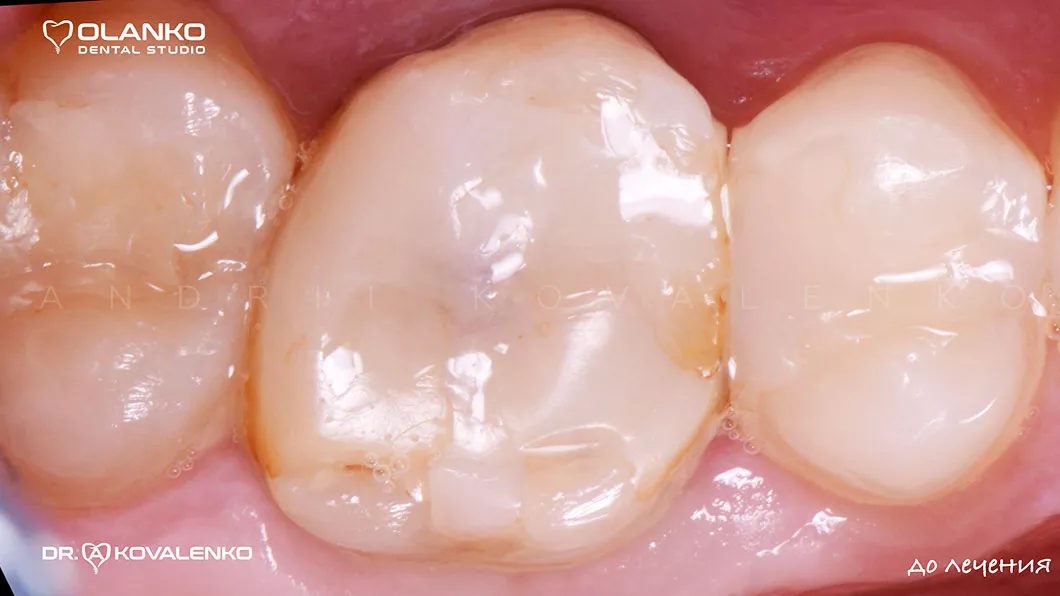

Лечение корневых каналов зуба с использованием микроскопа, на сегодняшний день, является золотым стандартом мировой стоматологической практики. Сложная система корневых каналов в зубе имеет очень малый диаметр и индивидуальную анатомию, поэтому врач, работающий без увеличения, не может качественно очистить и найти все корневые каналы на ощупь.

Важным преимуществом Olanko dental studio (Оланко) г. Бровары является то, что выполнение всех этапов лечения корневых каналов мы проводим только под контролем операционного дентального микроскопа!